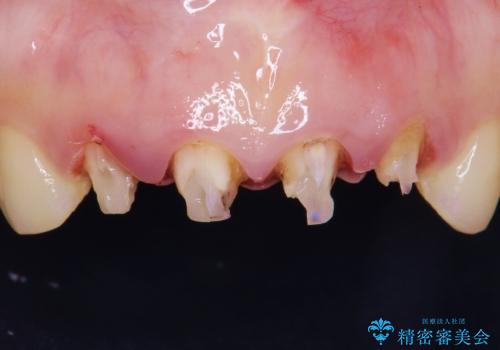

前歯4本の被せものは連結されており、不自然なだけではなく清掃性も悪く歯茎が著しく腫脹していました。

レントゲンを撮影したところ土台の植立も不十分であったため、土台からやりかえることにしました。

歯茎の腫脹が顕著であったため、適合の良いオーダーメイドの仮歯に変え、歯茎の状態が良くなるまで1ヶ月待ったのち型取りを行いました。